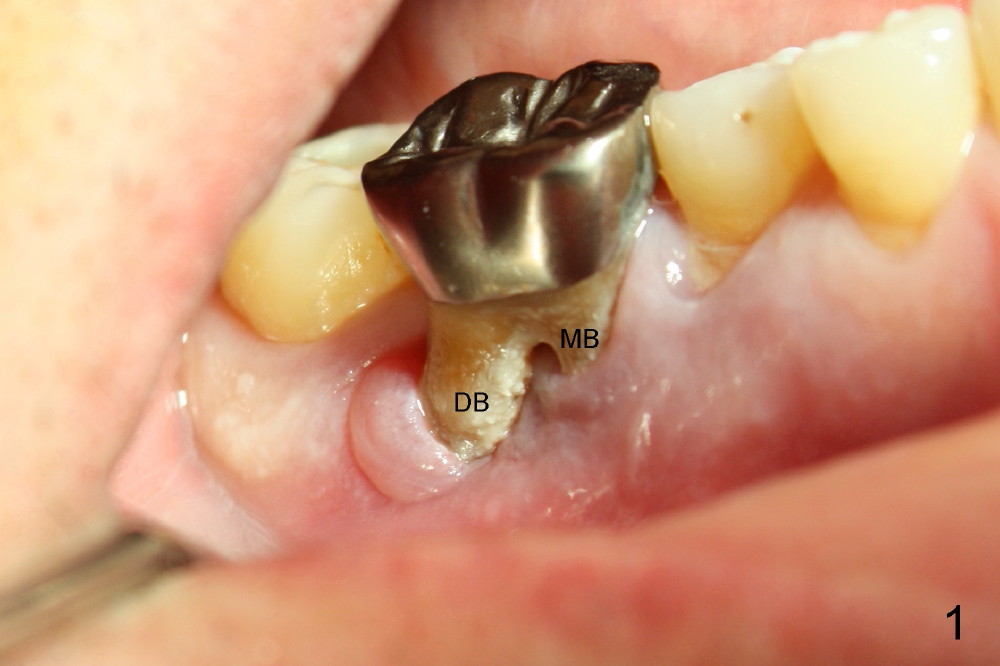

A 61-year-old man has severe periodontal disease. The lower right first molar is compounded by endodontic lesion. The distobuccal (Fig.1 DB) and distolingual (Fig.2 (mirror image) DL) roots are exposed.